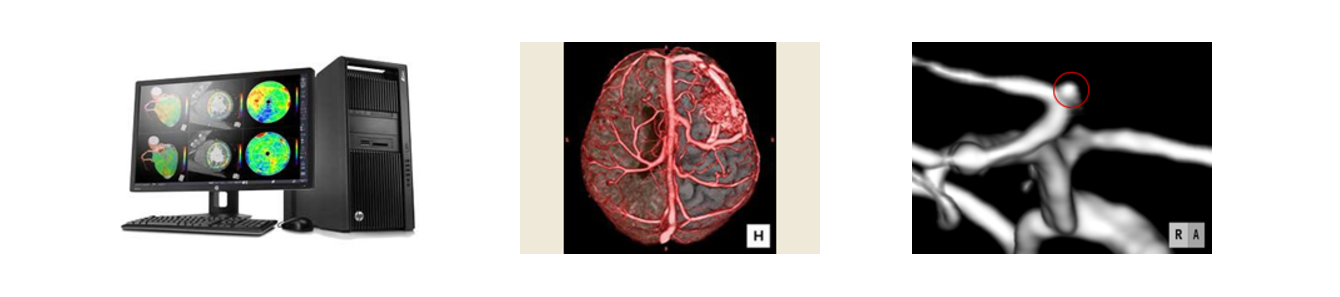

現代の三大疾患は「脳血管疾患(脳卒中)」「心臓病」「癌」といわれております。 脳卒中は、発症してしまうと命の危険があるだけでなく、救命できたとしても、その後重篤な後遺症が残る病気です。発症してからの治療では遅く、「発症を予防する」ことが重要となります。 検査は、MRI(磁場を利用した脳病変の診断方法)やMRA(脳の血管病変の観察方法)などの画像検査で行なわれます。 高血圧、糖尿病、肥満、あるいはご家族に脳卒中になられた方が居られるなどの危険因子がある方は、40歳を過ぎたら一度、脳ドックを受診されることをお勧めいたします。 ご自身の脳の状態を知る貴重な機会です。

無症候性脳梗塞(隠れ脳梗塞)

脳ドックで初めて発見されることが多い病気のひとつに、無症候性脳梗塞(隠れ脳梗塞)と呼ばれる、自覚症状が出現していない脳梗塞があります。発症は加齢と共に増加する傾向が強く、脳ドックを受けた70歳代のおよそ20%の人に発見されると言われています。特に、高血圧や糖尿病、脂質異常症(コレステロールや中性脂肪の高い方)のある方や不整脈(心房細動)のある方は要注意です。

無症候性脳出血

無症候性脳梗塞同様に、自覚症状の出ない無症候性脳出血があります。脳の中でも出血しても症状が現れにくい部分での少量出血の場合にみられます。最近は、MRIでのみ見つけることが出来る微小出血が見つかると、後に大きな出血の原因になる場合があることもわかってきました。

未破裂動脈瘤

脳動脈瘤とは、脳の動脈の一部が膨らんでできた瘤です。例えば風船が大きく膨らむと破裂しやすくなるように、動脈瘤も膨らむと破裂しやすくなります。主に血管が枝分かれしている部分(分岐部)に発生します。未破裂動脈瘤は破裂前の状態を言います。一般的には自覚症状は出ないため脳ドックで発見される場合がほとんどです。 必ず破裂するわけではありませんが、破裂すると、くも膜下出血となり死に至る病気ですので要注意です。経過観察をする場合と、手術や血管内治療などの外科的処置を行う場合があります。日本脳ドック学会のガイドラインでは、平均寿命から考えて余命が10~15年あり、未破裂動脈瘤の大きさが5~7mm以上の場合には、治療を考慮すべきとされています。